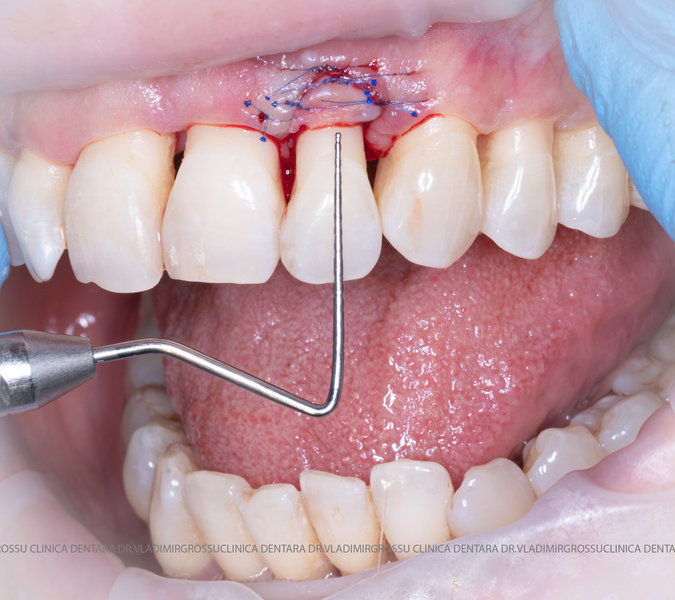

Aditia gingivală este o procedură chirurgicală ce corectează diverse probleme estetice și funcționale, cum ar fi recesiunea gingivală. În implantologia modernă, aditia de țesut moale este utilizată aproape în fiecare intervenție de inserție a implantului dentar pentru a asigura un aspect estetic natural și o bună integrare a implantului în cavitatea bucală.

Adiția osoasă are un rol crucial pentru poziționarea corectă și stabilă a implanturilor dentare. Clinica stomatologică Dr. Grossu din Chișinău promovează o abordare chirurgicală estetică și predictibilă, adaptată fiecărui caz în parte.

Medicii noștri au o vastă experiență atât în chirurgia estetică, cât și în protezarea cu un grad înalt de naturalitate, ceea ce ne permite să gestionăm cu succes și cele mai complexe cazuri.